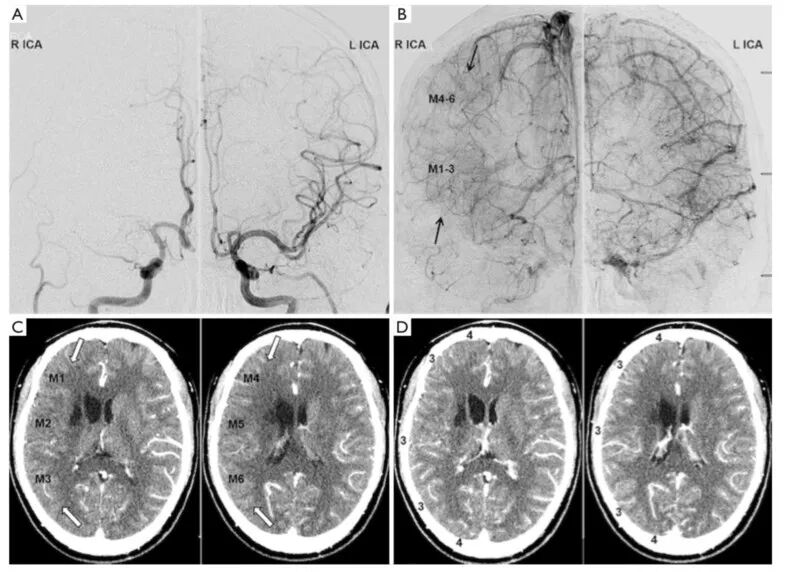

根据阿尔伯塔卒中规划早期CT评分(Alberta Stroke Programme Early CT Score)将大脑半球分为10个解剖区域。采用美国介入和治疗神经放射学会/介入放射学会(American Society of Interventional and Therapeutic Neuroradiology/Society of Interventional Radiology,ASITN/SIR)提出的侧枝代偿0-4级的5级法分级,由两位神经影像学医生通过DSA图像对10个解剖区域的侧枝代偿程度进行评级:0级,缺血区域无侧枝代偿;1级,缺血区域周围有缓慢发展的侧枝代偿,无灌注区;2级,缺血区域周边快速发展的侧枝代偿,无灌注区;3级,缺血区域侧枝代偿发展缓慢,静脉期可见血管显影;4级,侧枝代偿充分,并经逆行灌注至整个缺血区。由另两位神经影像学医生对10个区域CTP-Sis进行分级:0级,动脉期和静脉期缺血区均无增强;1级,缺血区边缘静脉期增强;2级,缺血区边缘动脉期增强,而静脉期有无灌注区;3级,缺血区静脉期完全增强;4级,缺血区动脉期完全增强(图2、3)。

图2. 侧枝代偿分级;DSA图像与CTP成像中各血供区域的对应关系。

图4. 侧枝代偿两种分级比较。22岁男性单侧烟雾病患者。双侧颈内动脉DSA的动脉期(A)和静脉期(B),显示右侧大脑中动脉延时显影(箭头,M1-6,3级);CTP-Sis分级:动脉期(C)中度强化(M1-6),静脉期(D)完全强化。白色箭头表示低灌注区域。患者侧枝代偿两种分级结果一致。